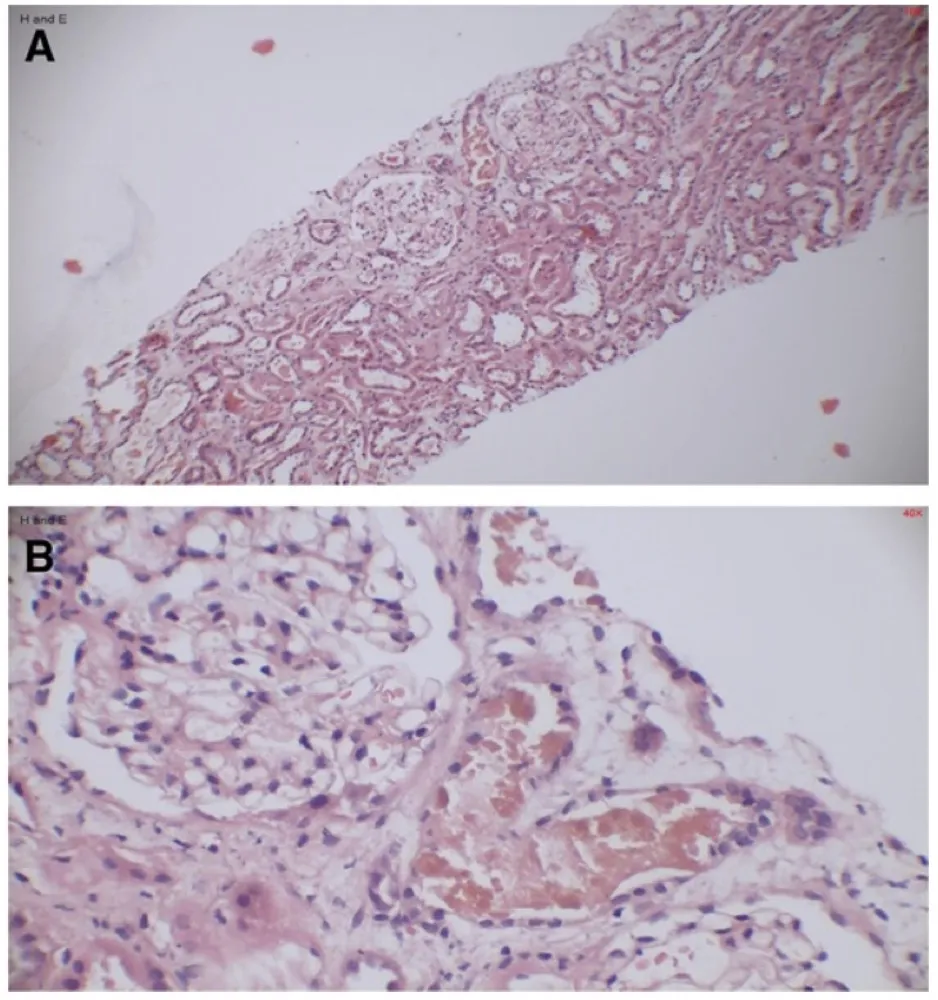

Idoso com GNRP, qual seria sua principal hipótese diagnóstica?

Idoso com GNRP, qual seria sua principal hipótese diagnóstica?Caso típico de GNRP em paciente idosos. Vendo a imagem, qual seria sua primeira hipótese diagnóstica?